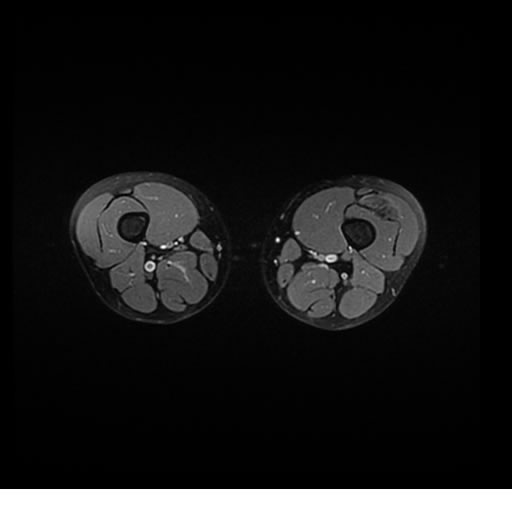

Se realiza estudio de MRI de pierna izquierda, utilizando secuencias Spin Echo y GRE en diferentes planos, se realiza angio MRI en fase arterial y venosa de pierna izquierda

El estudio demuestra masa a nivel de los músculos gemelos, más evidente en secuencia con pulso de saturación de grasa, en el estudio de angio resonancia de pierna la fase arterial no muestra ninguna anormalidad, en la fase venosa se observa acumulo del medio de contraste a este nivel.

Se concluye que se observa una masa de tejido muscular sumamente vascularizada compatible con un hemangioarcoma.